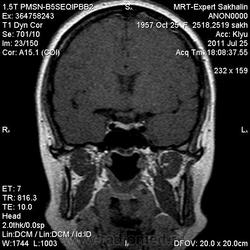

Женщина.6 лет назад выявлено образование левой доли нейрогипофиза.Пришла на контроль.

Постконтраст

Мне самой показался случай не совсем ясным, но динамик четко показывает участок с отставанием в контрастировании, воронка смещена вправо-о чем  думать бедному начинающему специалисту?